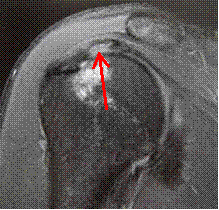

Partial Thickness Tear